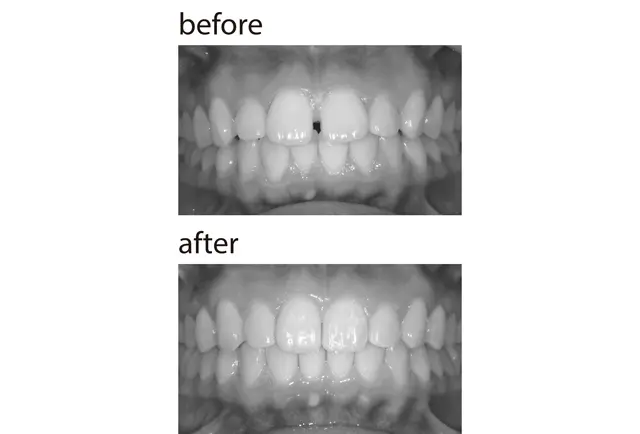

奥歯4本ずつの銀歯をセラミックに変え、前歯には裏側ワイヤー矯正も。人に見せたくなる仕上がりに